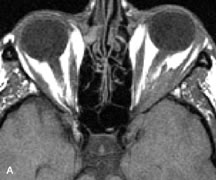

Breast carcinoma metastatic to the orbit has been demonstrated to be hypointense to the surrounding orbital fat on T1-weighted studies and hyperintense on T2-weighted images and has an affinity to the extraocular muscles (Fig. 20).50,64 The MRI characteristics of prostate carcinoma metastatic to the orbit have been described as involving the greater and lesser wing of the sphenoid, orbital roof, and optic canal. Diffuse bone hypertrophy with isointense or slightly hyperintense tissue on T1-weighted images represents the osteoblastic carcinomatous bone infiltration. Contrast enhancement is variable on T1-weighted and fat-suppressed images.65

Fig. 20. A. T1-weighted MR scan demonstrates nodular enlargement of both medial rectus muscles (arrows). B. T1-weighted fat-suppressed contrast-enhanced scan confirms the presence of small metnstatic deposits within the muscles (open arrows).